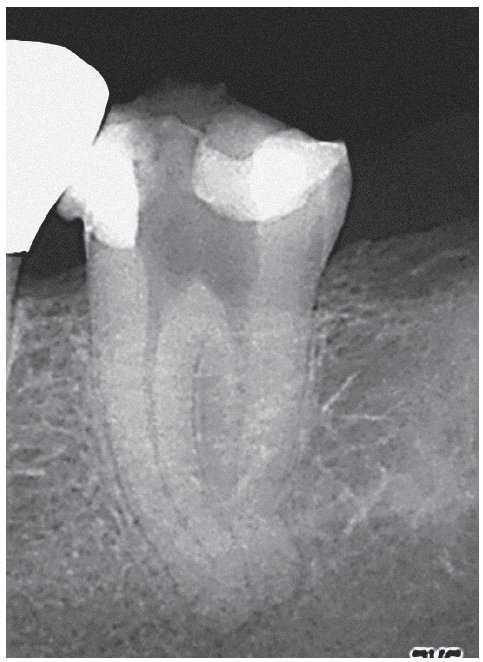

Figura 2a. La radiografía diagnóstica del diente 47 muestra una periodontitis apical postendodóntica.

Figura 2b. En sentido vestibular ya se observa un trayecto fistuloso.

Figura 2g. Situación después de la obturación termoplástica. Los istmos también muestran un buen sellado marginal.

Figura 2h. Radiografías de control después de la obturación: el tamaño de la luz obturada es considerablemente mayor en comparación con el tratamiento inicial. Se consiguió una obturación homogénea de los dos istmos situados en la parte coronal y apical de la raíz mesial.

Figura 2i. La radiografía de control realizada a los 12 meses mostró una curación ósea completa de la lesión apical.